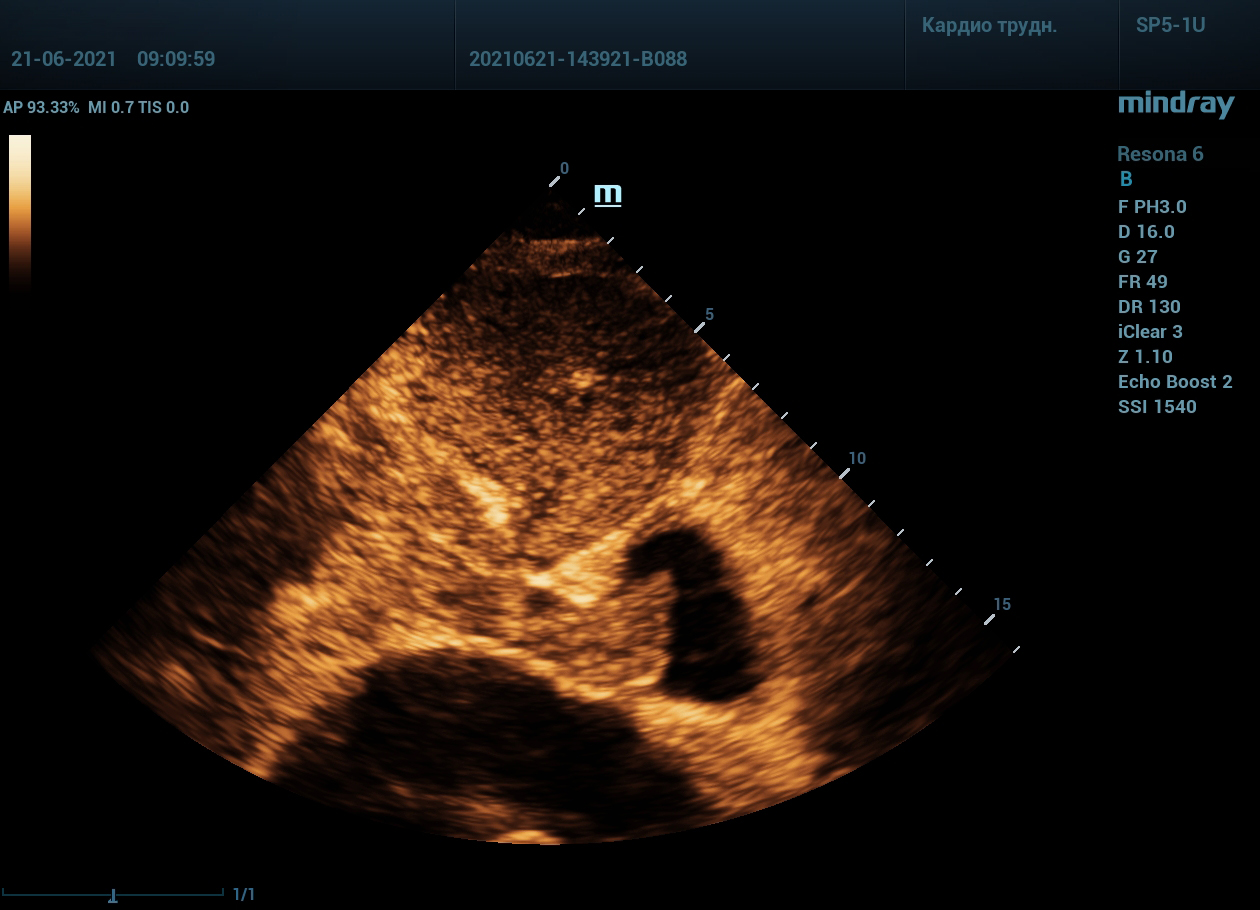

Интересный случай из практики нашего врача-аппликатора. Использовался экспертный ультразвуковой прибор Mindray Resona 6, стандартные заводские пресеты и автоматическая оптимизация iTouch. В эхокардиографии всегда помогает колорайзинг, чаще всего используется оранжевый оттенок. Пациент обследуется перед оперативным лечением по поводу онкологии почки. Вены нижних конечностей у данного пациента без особенностей, сжимаемы и проходимы. Казалось бы, проблема тромбоза миновала но в процессе эхокардиографического исследования, при сканировании нижней полой вены в субкостальном сечении, определяется эхогенное образование. Образование на месте просвета нижней полой вены. Вена расширена, эхогенное включение проникает в правое предсердие. По краю тромба в цветопотоковой визуализации определяется кровоток. Онкологическое заболевание почки осложнилось тромбозом почечной вены, с распространением тромба в нижнюю полую вену и правое предсердие. Изюминку добавляет то, что в других эхокардиографических сечениях тромб совершенно не виден.